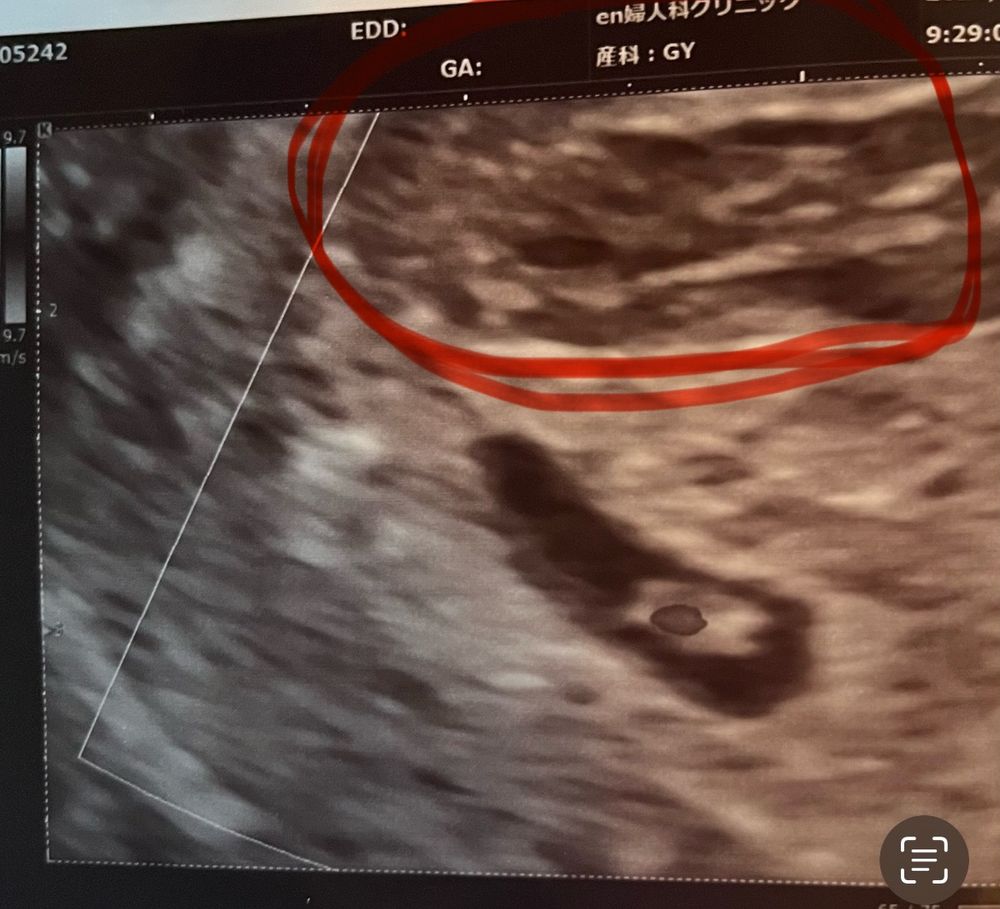

Сохранение ЭКО-беременности26 дпп и снова алая кровь. В этот раз не течет, но остается на туалетной бумаге. Я читала, что кровь должна быть коричневой, а не алой. У меня она никогда не была коричневой. Всегда алая, после транексама бордовая, иногда выходит кусочками. Вчера на узи впервые увидели большую гематому с кусками крови внутри… повысили дозу дюфастона, врач успокоила, сказав что кровать будет долго, так что сильно переживать не стоит. Но все же, почему только алая кровь. Кровь появляется каждые 2 дня с 18 дпп, проходит после транексама и все по новой через день…

Вроде как гематома далеко от ПЯ, но я волнуюсь. У кого она тоже выходила алой кровью?